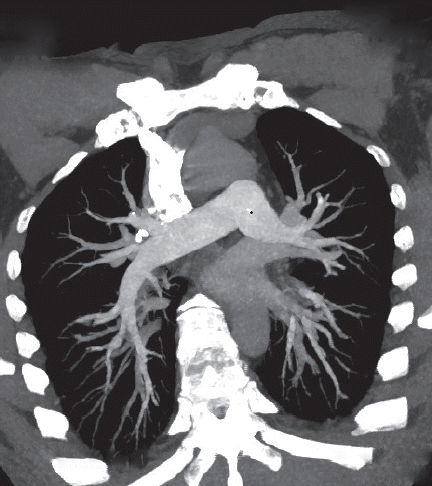

A 46-year-old male complaining of edema for 2 months and exertional dyspnea and chest pain for 2 weeks was admitted to our hospital. The patient denied abdominal pain, nausea, and loss of appetite. He had no history of diabetes mellitus, hypertension, or malignancy. Initial laboratory studies showed that his hemoglobin level was 11.1 g/dl. Urinalysis revealed yellow urine with proteinuria 7,588 mg per day. CT angiogram (CTA) of lungs showed multiple pulmonary embolism (

Fig. 1). The patient was given warfarin for pulmonary embolism, glucocorticosteroids and tarcrolimus for primary nephrotic syndrome. After 10 days, the patient presented with acute hematochezia and dizziness without obvious abdominal pain. The gastrointestinal bleeding did not stop when warfarin was stopped and treated with Vitamin K. On physical examinations, the patient’s vital signs were stable on admission. However, his blood pressure was falling quickly after he got admitted with acute gastrointestinal bleeding. His abdomen was soft. Bowel sounds were normoactive. Several external hemorrhoids were evident but without bleeding. Laboratory results were as follows: hemoglobin 11.1 g/dl on admission, fell to 3.8 g/dl in his 20 days of gastrointestinal bleeding; white blood cell count, 7.05×10

Fig. 1CT angiogram showing multiple pulmonary embolism.